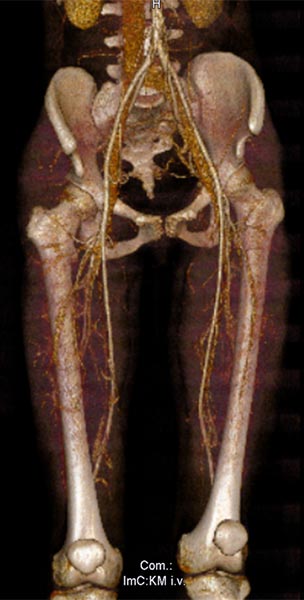

In der 3D-Darstellung der computertomographischen Angiographie findet sich ein normaler Befund der rechtsseitigen Arterien und Venen der Leiste und des Oberschenkels. Diese sind nicht an der Malformation beteiligt. Auch die darunter liegenden knöchernen Strukturen sind unauffällig.